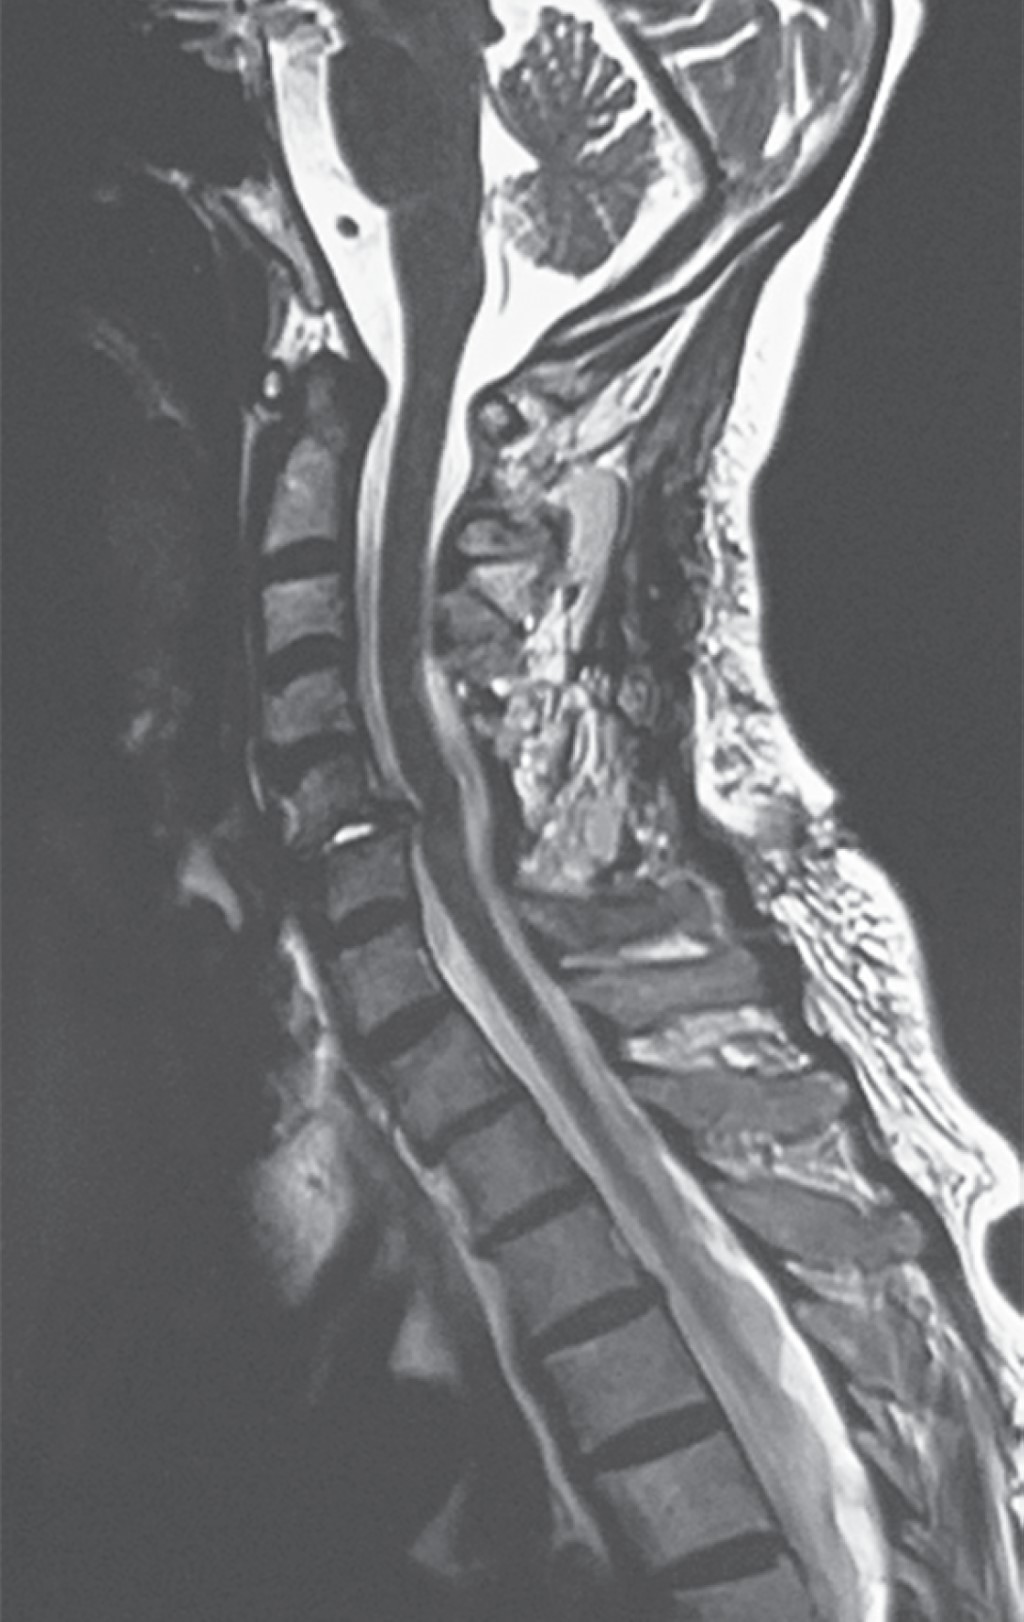

Subaxial cervical spine luxation is a frequent entity in polytraumatized patients, regularly accompanied by neurological injuries such as paraplegia or quadriplegia, requiring urgent surgical treatment in order to stabilize, align and decompress the nerve structures, sometimes it is not possible to perform this type of procedure early due to the general conditions of the patient or the conditions of the hospital units, leading to a late treatment, however, undiagnosed luxation occur, or in the worst case scenario, an inadequately treated injury with poor results that lead to an unsatisfactory evolution of the patient, with chronic pain and neurological deficit. We analyze the case of a patient with subaxial cervical spine luxation, with torpid evolution, requiring a new intervention two years after her injury, performed in three specific sequential times, achieving the patient's recovery and motor functionality.REFERENCES